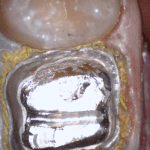

In this clinical video we demonstrate how to scan a molar preparation for the replacement of a crown with recurrent decay and open margins. The molar was root canal treated and the tissue was inflamed. the preparation was imaged and a temporary was fabricated to allow the tissue to heal properly.

The main point of this video is to show how to capture the contacts of the adjacent teeth and the deep marings